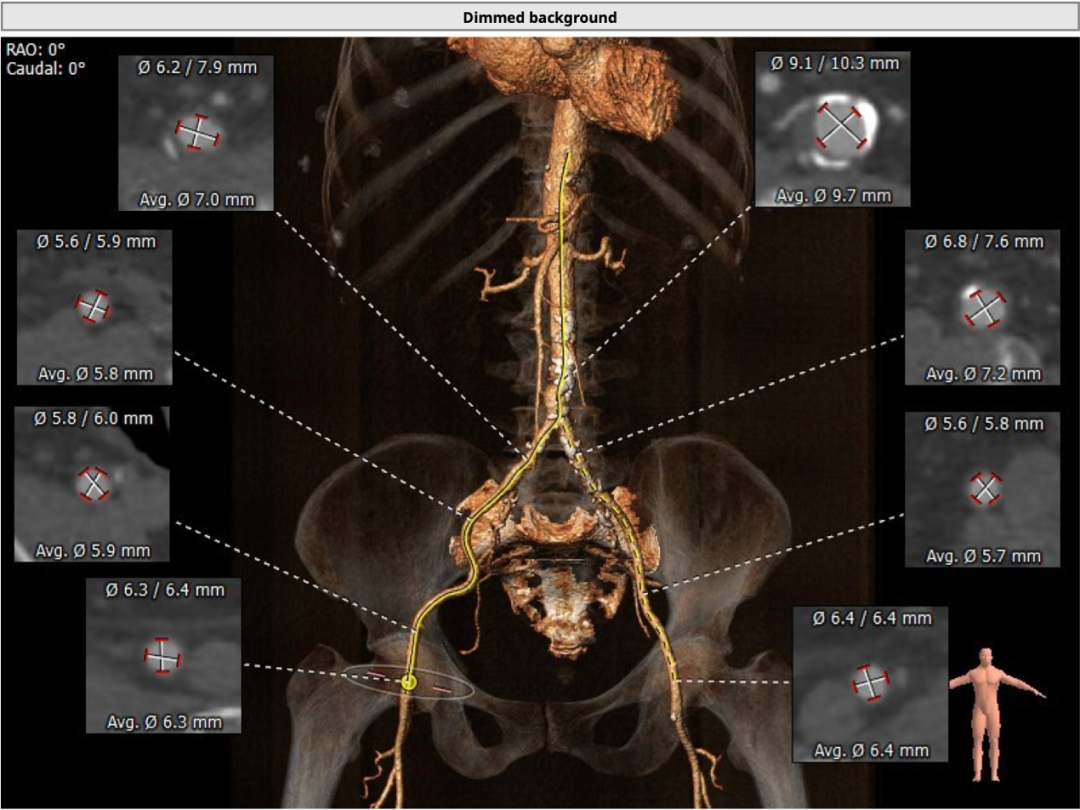

术前CT

为TYPE1型二叶式主动脉瓣,左右融合钙化嵴,钙化较重,瓣环周长获得平均直径25.1mm,左右冠脉开口高度分别为11.1和16.1mm。左冠开口水平可见瓣叶,有堵塞风险。双侧股动脉无明显钙化迂曲,左右最细处分别为5.7和5.8mm。

为三叶式主动脉瓣,瓣叶钙化较重,瓣环周长获得平均直径23.5mm,左右冠脉开口高度分别为11.2和16.4mm。瓣叶冗长,左冠开口水平可见瓣叶,左冠有堵塞风险。双侧股动脉走行流畅,无明显钙化迂曲,左右最细处分别为6.5和6.6mm。